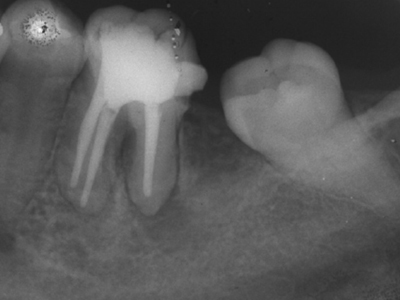

Clinical & Radiographic Monitoring :

Healing is assessed by clinical signs and radiographic changes in the periapical tissue over time, with complete healing sometimes taking several years